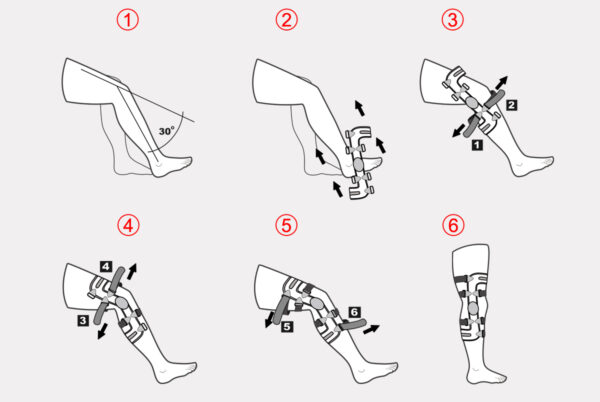

INSTRUKCJA ZAKŁADANIA ORTEZY „RAPTOR 2RA“

1. Odblokować zegary boczne w celu uzyskania maksymalnego zakresu zgięcia i wyprostu ortezy.

2. Porozpinać i powysuwać z klamerek poszczególne pasy mocujące.

3. W celu wyeliminowania przypadkowego plątania się pasów, po odpięciu i wysunięciu danego pasa z klamerki, należy powtórnie przypiąć do niego zakończenienie rzepowe.

4. Ustawić kończynę pacjenta w zgięciu ok. 120 stopni i wsunąć ortezę na kończynę dolną.

5. Przepleść przez klamrę poliamidową i zapiąć przedni dolny pas goleniowy oznaczony numerem (1)

6. Ustawić zegar ortezy dokładnie w osi stawu kolanowego , przepleść przez klamrę i dopiąć tylny pas udowy oznaczony numerem (2)

7. Przepleść przez klamrę i dopiąć tylny pas udowy oznaczony numerem (3) Uwaga; napięcie tylnego pasa powoduje przesunięcie zegara do tyłu, i dlatego należy tak dobrać napięcie pasa alby po jego zapięciu zegar znajdował się dokładnie w osi stawu kolanowego.

8. Zgiąć staw kolanowy do ok 70 stopni i w takiej pozycji mocno dopiąć przedni pas podkolanowy oznaczony numerem (4), zwracając uwagę by miękka osłona antypoślizgowa znajdowała się na środku goleni.

9. Wyprostować kończynę i dopiąć tylny pas łydkowy oznaczony numerem (5).